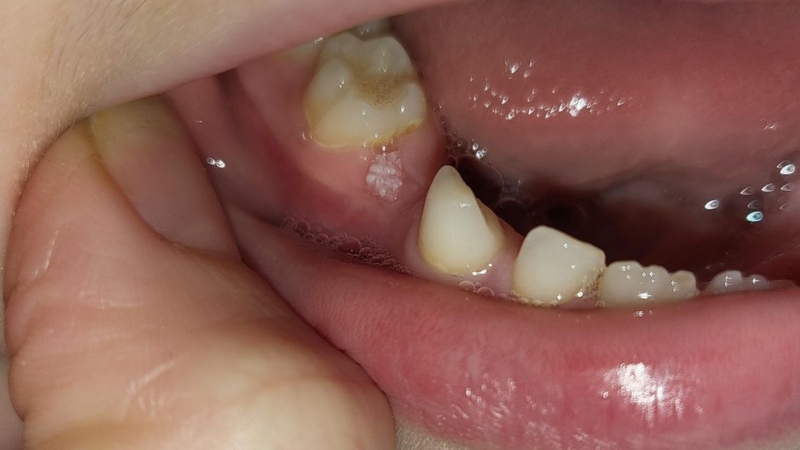

Nướu răng xuất hiện các u nhú, sưng đỏ bất thường nhưng không gây đau có thể là dấu hiệu cảnh báo sùi mào gà ở nướu răng. Việc phát hiện sớm và điều trị đúng cách giúp kiểm soát bệnh và phòng ngừa biến chứng nguy hiểm.

Có thể nhận biết sớm sùi mào gà ở nướu răng qua những dấu hiệu sau:

Sùi mào gà ở nướu răng tuy không gây đau cấp tính nhưng ẩn chứa nhiều nguy cơ nếu không được phát hiện và điều trị kịp thời. Ban đầu, các tổn thương u nhú có thể xuất hiện nhỏ lẻ và ít gây khó chịu. Tuy nhiên, nếu để kéo dài, chúng có xu hướng lan rộng nhanh, liên kết thành cụm lớn, gây chảy máu, nhiễm trùng và rất khó kiểm soát.